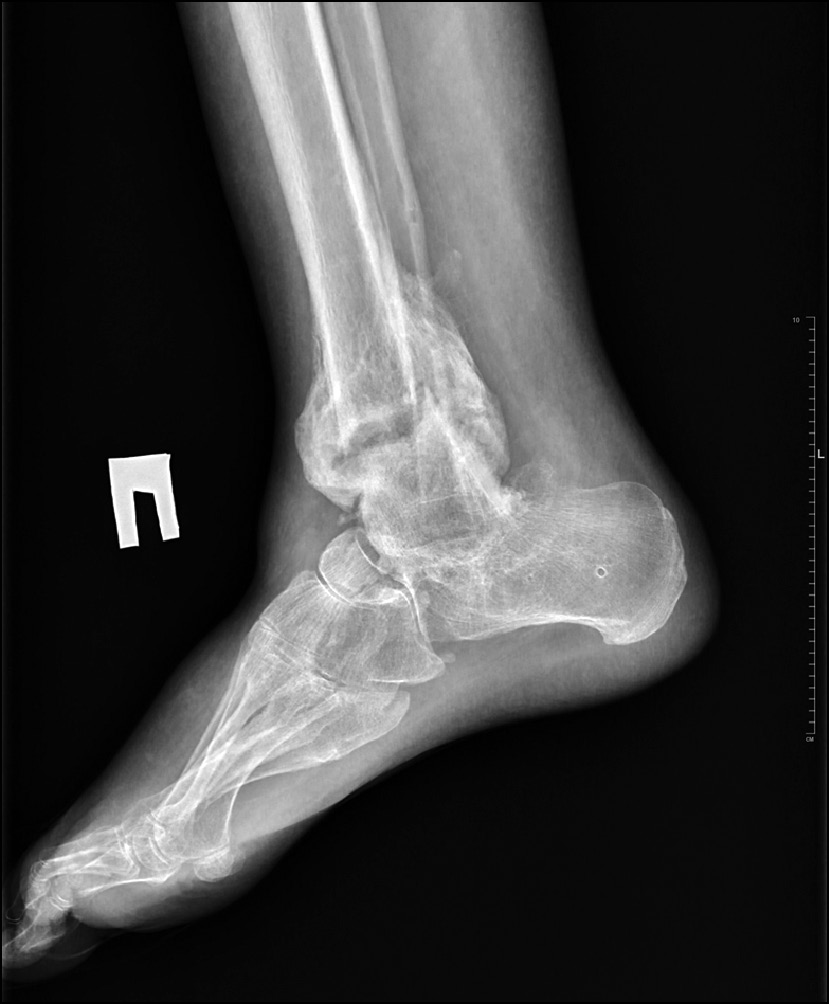

При рентгенологическом обследовании выявлен лизис таранной кости правой стопы на 2/3 от своего объёма (преимущественно тела таранной кости) со слабо выраженными признаками снижения МПКТ: истончение кортикальной пластинки, крупноячеистая трабекулярная микроструктура, усиленная рентгенопрозрачность (рис. 2, 3).

Рис. 2. Рентгенограмма в передне-задней проекции до лечения.

Fig. 2. X-ray image in anterior-posterior projection before treatment.

Рис. 3. Рентгенограмма в боковой проекции до лечения.

Fig. 3. X-ray image before treatment in lateral projection.